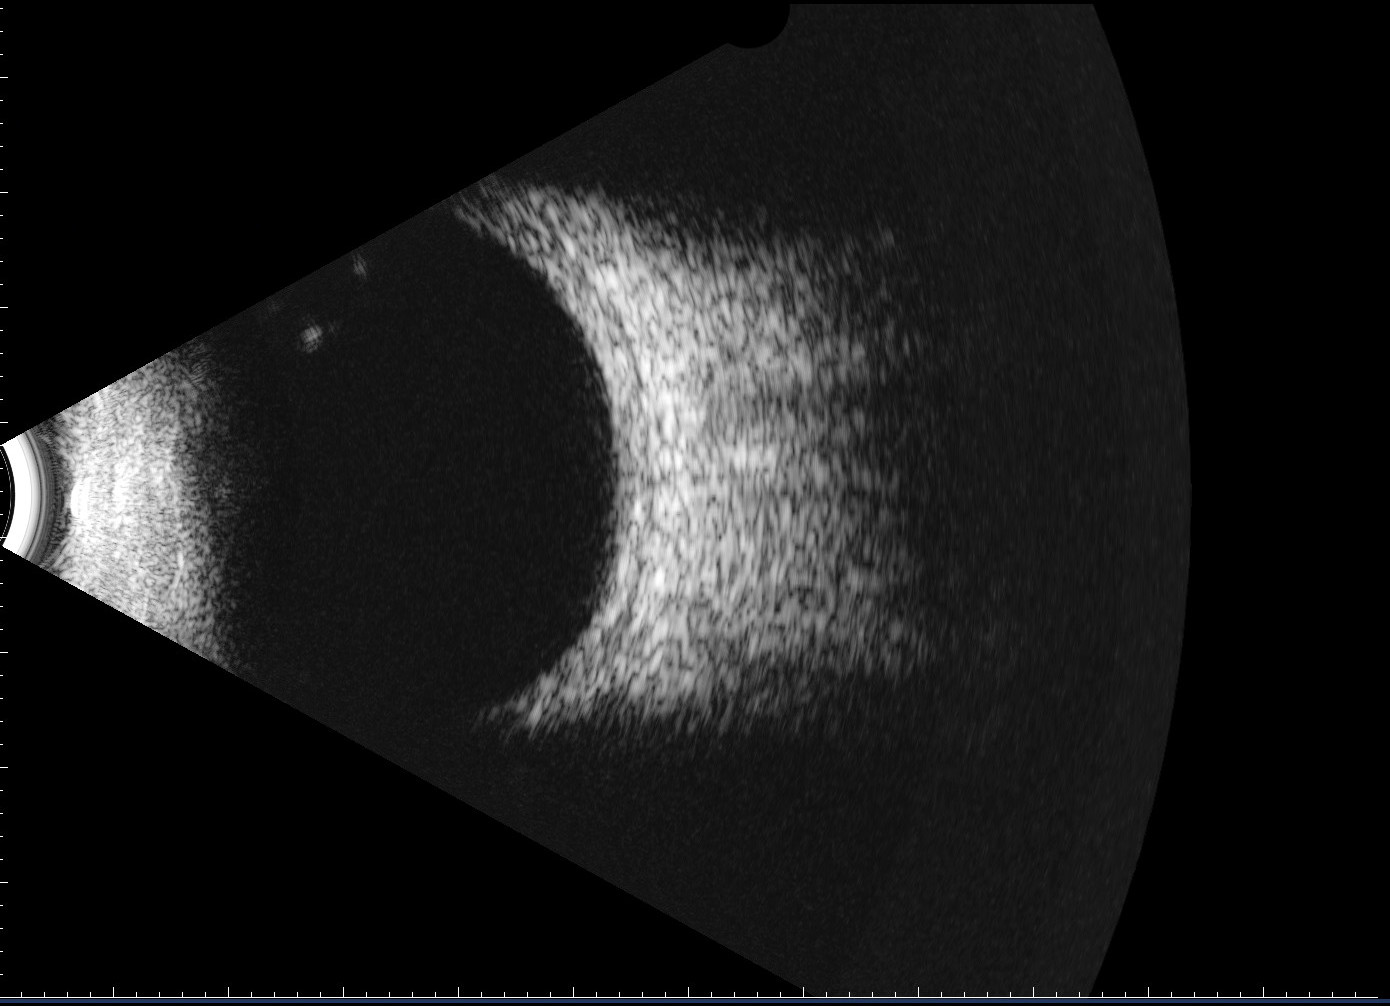

• B-Scan Ultrasound

B-scan_cropped

Full size 1390 × 1006

Published inB-Scan Ultrasound